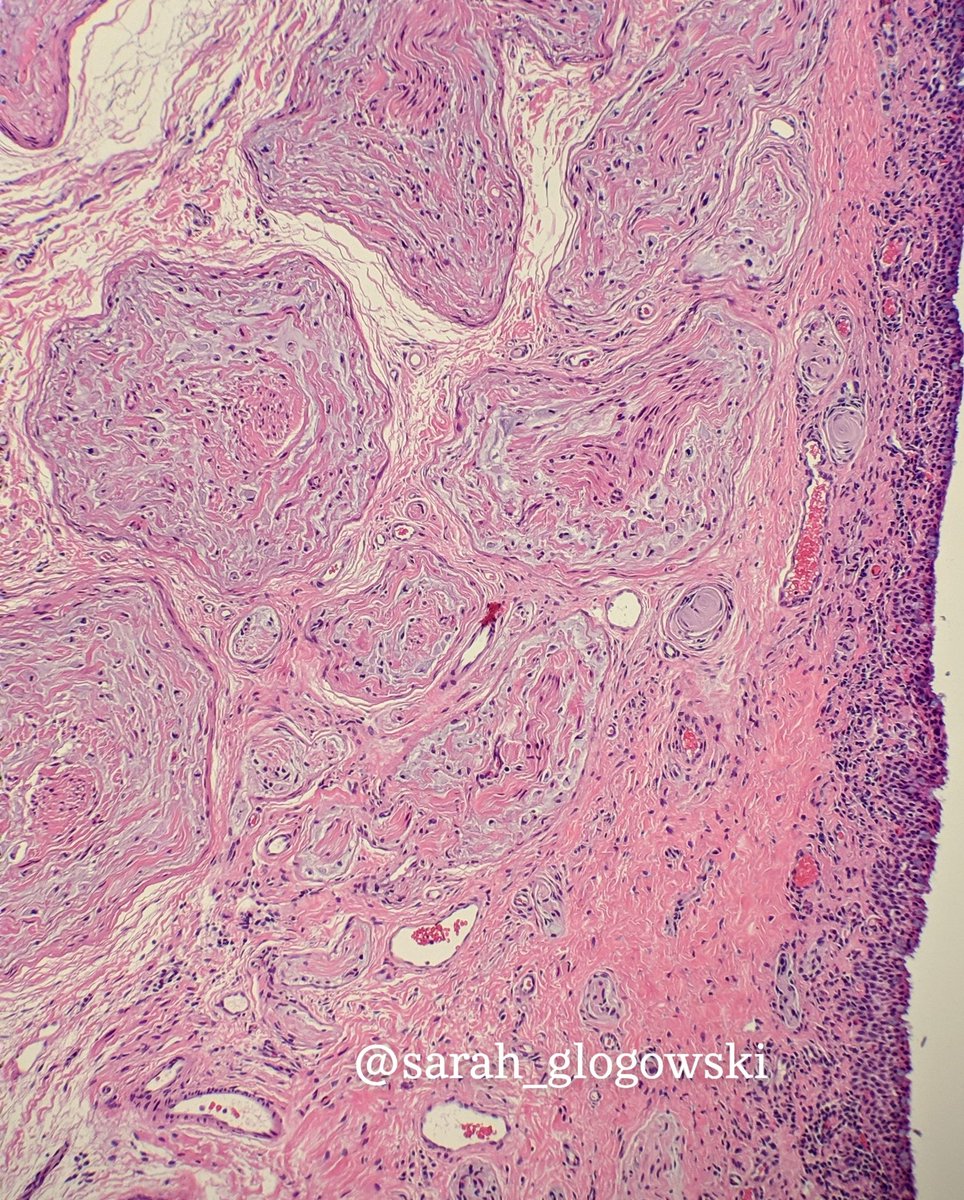

5 year old male with a frontal lobe lesion.

Differential? Work up? #neuro#pathology#neurosurgery#neuropath#brain#CNS#surgery

No mitosis seems. MIB <1%. No history that we know of TSC. Waiting on molecular results. Diagnosed as a Ganglioglioma Grade I.

#pathology#neuro#neurosurgery#brain#neuropathpic.twitter.com/ewjpJz0BAm